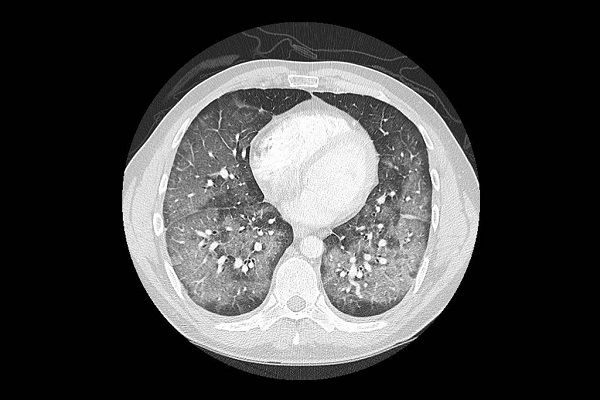

En las tomografías pulmonares, las enfermedades al principio lucen como una neumonía viral o bacteriana grave, pero los análisis no dan señales de infección. “Hemos llevado a cabo muchas pruebas buscando bacterias y virus, pero dan negativo”, dijo Dixie Harris, neumóloga de cuidados intensivos en Salt Lake City, que ha examinado a cuatro pacientes que sufren ese padecimiento y revisó los archivos de nueve más en el estado.

Algunos pacientes sufren otro padecimiento conocido como neumonía lipoidea, dijeron los médicos. Cuando los aceites vapeados llegan a los pulmones, estos los tratan como un objeto extraño y detonan una respuesta inmune, que provoca inflamación y la acumulación de líquidos, lo cual puede resultar en una neumonía lipoidea.